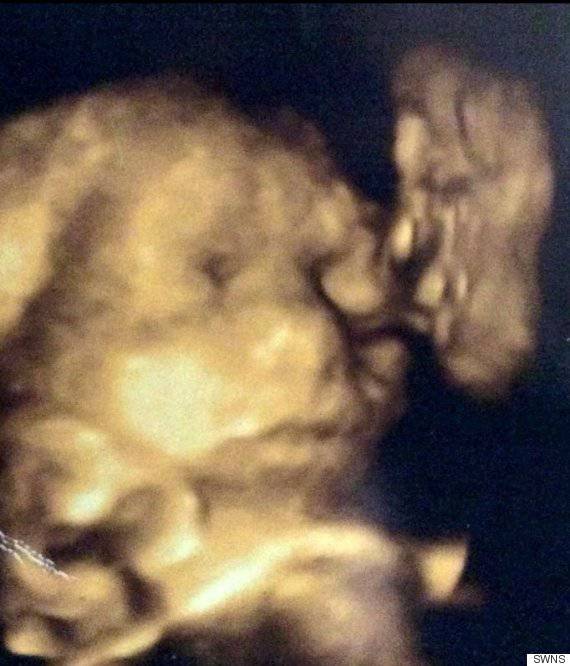

ecografia 4dSappiamo che le ecografie dei nostri piccini ancora nel grembo spesso non sono particolarmente chiare, ma la mamma Jade Hornsby ha avuto davvero un’incredibile sorpresa.

La donna si è recata in un ospedale londinese per avere un’ecografia in 4d della sua piccina, ma quando ha guardato l’immagine ha notato una strana forma in un angolo.

Dopo uno sguardo più approfondito la donna ha stabilito che quella forma somigliava davvero molto al profilo di suo nonno: Jack Hornsby, deceduto nel 2007.

Si tratta di una cosa davvero inquietante. Gli somiglia davvero tanto e lo si può vedere più chiaramente di mia figlia” ha dichiarato la donna via Huffington Post.

Le sue labbra sono corrugate come se si accingesse a darle un bacio sulla guancia. Si possono vedere gli occhi, il naso e la bocca”.